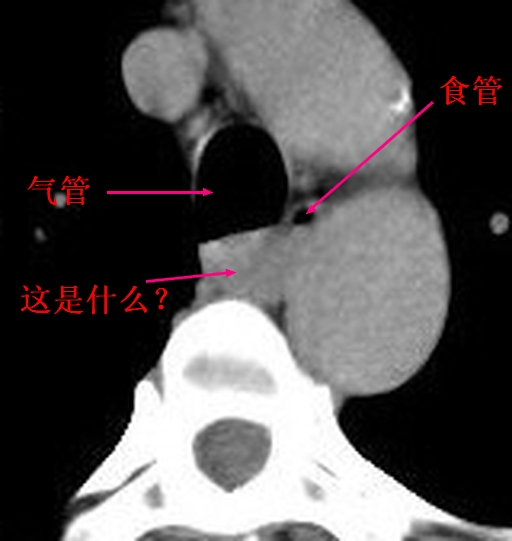

食管或气管囊肿可能性大。

支气管(或食管)囊肿?肿大之淋巴结?神经源性肿瘤?

神经源性肿瘤基本可以排除,因为病变没有强化。现在的问题是,病变考虑不考虑肿大淋巴结呢?因为病变的环周也没有强化,我们的意见也不考虑。这样的话,患者就需要手术处理了。希望高手还能谈谈各自的高见!

考虑气管囊肿可能性大。

考虑 1淋巴结 2气管或食管囊肿 3食管良性肿物